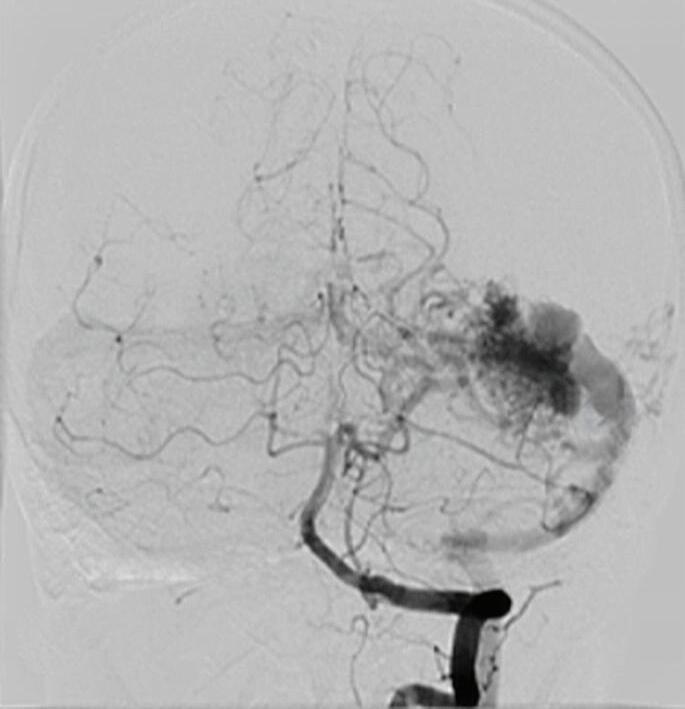

Fig. 1-20. RNM T1 com contraste em cortes (a) axial e (b) sagital e (c) FLAIR axial, demonstrando MAV do giro fusiforme esquerdo com presença do aneurisma pós-nidal (setas azuis). Angiografia pré-operatória em (d) AP e (e) em perfil mostrando a MAV anteriormente descrita, nutrida por ramos da artéria cerebral média e posterior esquerda, com drenagem superficial para o seio transverso e sigmoide ipsilateral e aneurisma pós-nidal venoso (setas azuis). (f) Visão intraoperatória do aneurisma pós-nidal (seta azul).